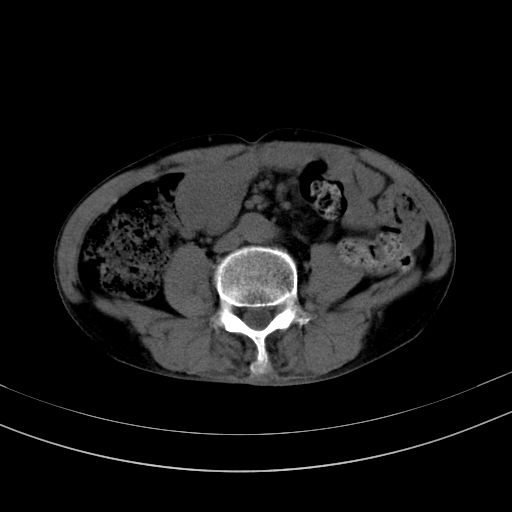

以下是引用37度在2010-1-9 14:37:00的发言:[br]1.双肾囊肿,左肾积水结石,.胆总管轻度扩张;[br]2.病灶在腹膜外,考虑纤维瘤。

以下是引用dyqct在2010-1-9 17:56:00的发言:[br]考虑:1.双肾囊肿,左肾积水结石、旋转不良。[br] 2.右侧腹直肌血肿或纤维瘤。[br]肠道准备不好。做个增强。